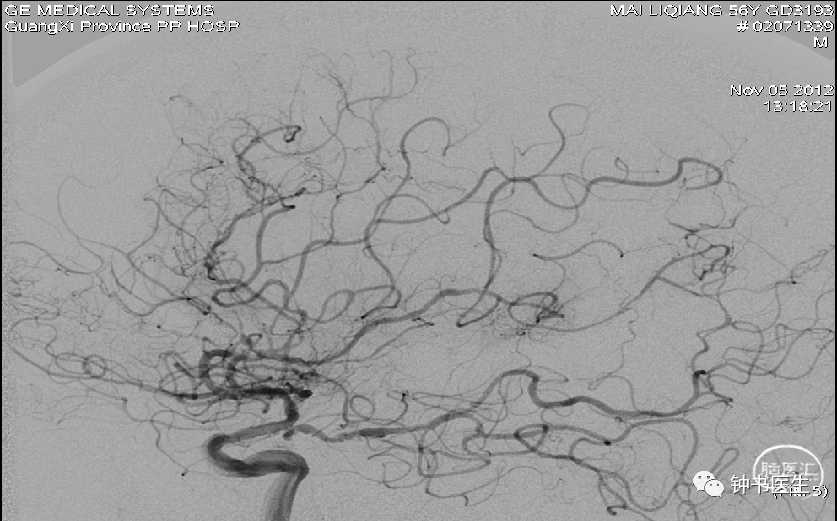

病例1

56y,意识不清伴右侧肢体无力5小时,GCS8分

再灌注损伤(出血):需降压

出血疼痛、烦躁,血压高

镇静镇痛影响神志观察

2012-11-8 CT

左颞部脑梗加重,出血渗出点增多。继续加强镇静镇痛治疗。

2012-11-10 CT

病情趋稳定,转出监护室治疗。